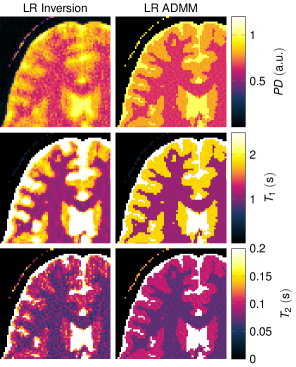

Reconstructions with R=20๐‘…20R=20

Fig. 8 compares the low rank inversion and the ADMM algorithm for R=20๐‘…20R=20 in order to further analyze the influence of the rank. In the case of the low rank inverse problem (Eq. (17)), spatial blurring can be observed, most prominently in the T1subscript๐‘‡1T_{1} map. This is also reflected in Fig. 2b, where the NRMSE increase at high R๐‘…R values is strongest for T1subscript๐‘‡1T_{1}. When employing the ADMM algorithm, some noise-like artifacts can be observed, but the blurring is reduced compared to the low rank inversion.

Figure 8

The displayed excerpts of quantitative maps compare low rank inverse reconstructions with R=20๐‘…20R=20. The simulations are based on a numerical phantom and were reconstructed from noise free data.

Figure 8: The displayed excerpts of quantitative maps compare low rank inverse reconstructions with R=20๐‘…20R=20. The simulations are based on a numerical phantom and were reconstructed from noise free data.